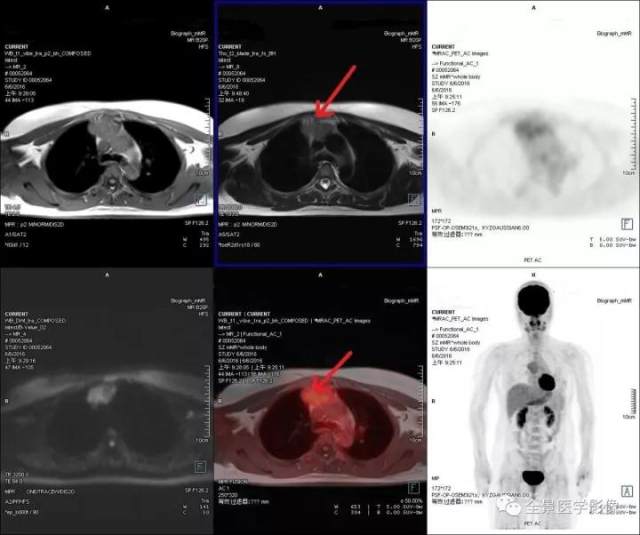

胸腺瘤

◆ 案例:中年女性,容易疲劳,一月前曾有上呼吸道感染史。PET/MR 发现胸腺区肿块最大横截面积约 4.8 cm*2.7 cm,FDG 代谢增高,术后病理:胸腺瘤。

点评:

胸腺瘤是纵隔常见的良性肿瘤,病灶较小 (<1 cm) 或者无明显 FDG 代谢增高的可以定期复查,如代谢增高建议咨询胸外科如何处理。